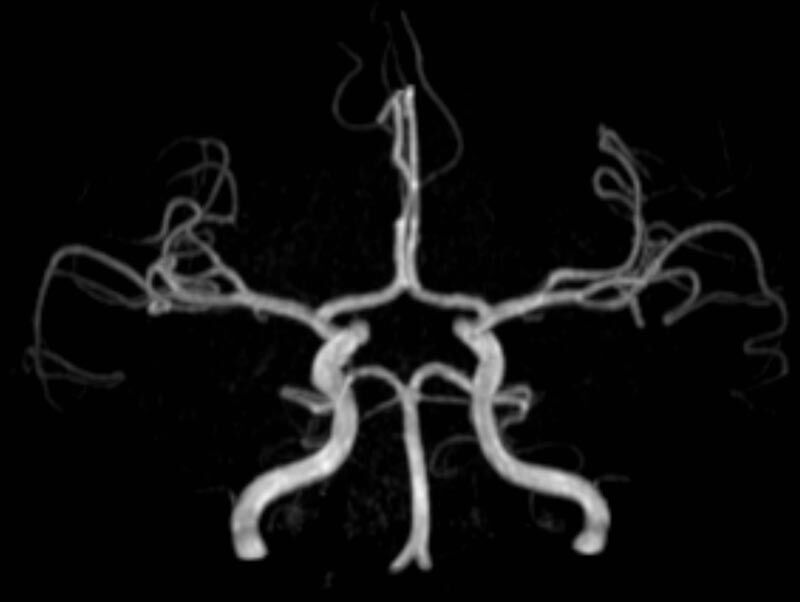

Kopf/Hals

• akute Schlaganfalldiagnostik und chronische Durchblutungsstörungen

• intrakranielle Gefäße (Abklärung Verschluss, Stenose, Aneurysma)

• Halsgefäße zur Therapieplanung (z.B. Stent, Operation)

MR-Angiografie (MRA)

• MR-Angiografie ohne Kontrastmittel

• Time of Flight (TOF)-Angiographie

Je nach Fragestellung und Körperregion Gefäßdarstellung ohne Kontrastmittel bei Kontrastmittelunverträglichkeit oder terminaler Niereninsuffizienz möglich.

• MR-Angiographie mit Kontrastmittel

• Erfassung arterieller und venöser Gefäße/Bypässe aller Körperregionen mit 3D-Rekonstruktion